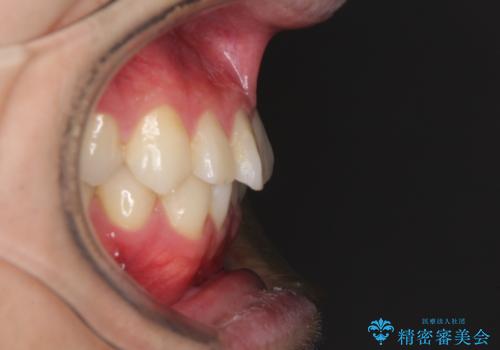

- 30代男性

- 矯正装置

- 審美装置

- 治療期間

- 1年2ヶ月

- 右下奥歯の虫歯がしみて痛いとのことで来院された患者様です。

神経近くにまで及ぶ大きな虫歯でしたが、速やかに処置を行い、痛みは即日解消されました。

虫歯が大きかったため、クラウンによる補綴治療が必要になる旨をお伝えしたところ、矯正治療にも興味があるとのことでした。

短期間で手間のかからない方法がご希望でしたので、ワイヤー装置による矯正治療を行うこととし、矯正治療後に右奥2歯をセラミッククラウンにて補綴することとしました。